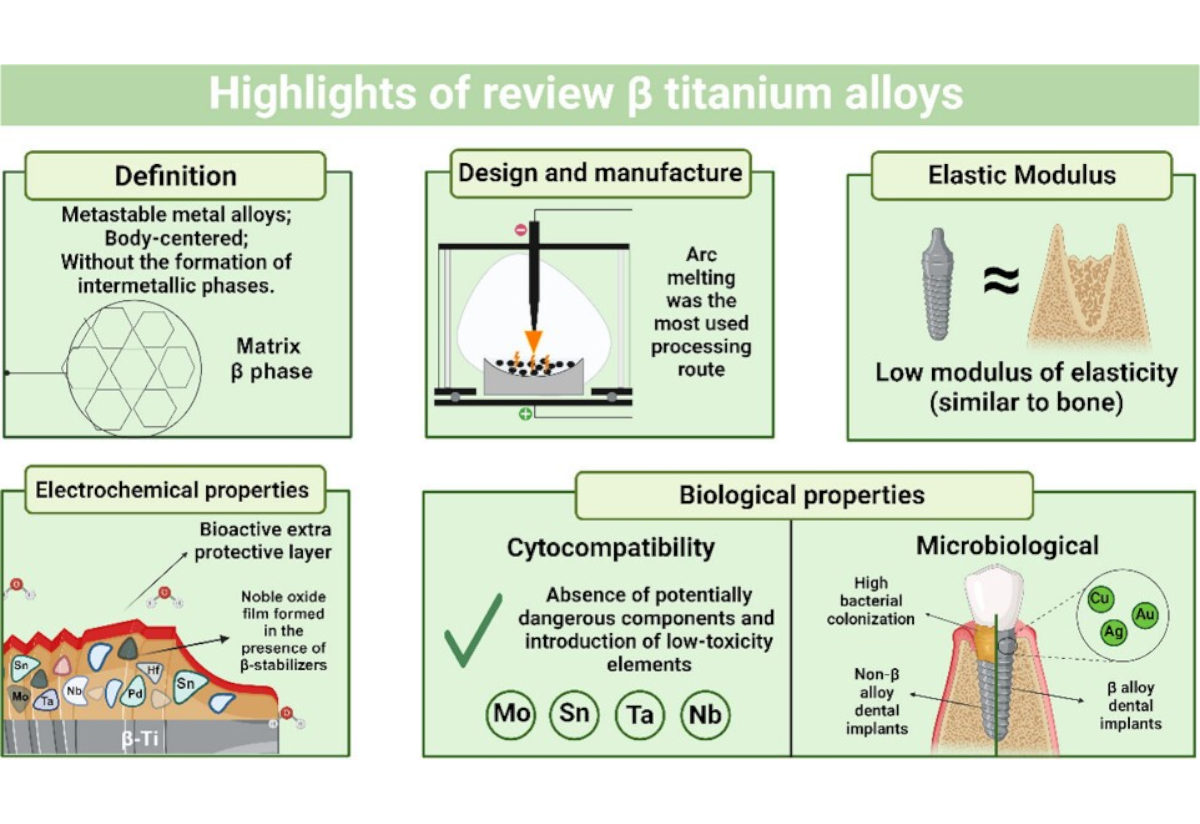

Diş İmplantları: Titanyum implantlar eksik dişlerin yerini alır ve porselen veya zirkonyum kronlarla doğal bir görünüm sağlar...